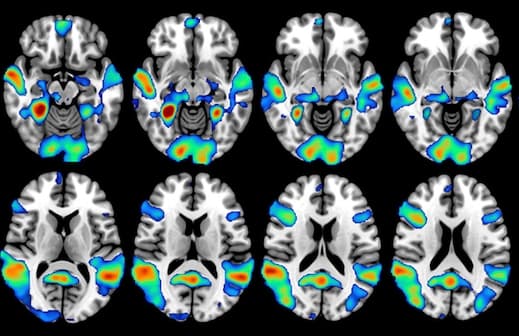

En étudiant l'activité cérébrale des supporters de football par IRM fonctionnelle, des chercheurs ont découvert que certaines régions du cerveau s'activaient lors du visionnage de matchs de leur équipe favorite, déclenchant des émotions et des comportements positifs et négatifs. Dans un article publié dans la Revue Radiology, ils suggèrent que ces schémas pourraient également s'appliquer à d'autres formes de fanatisme et que la prévention doit s’appliquer dès le plus jeune âge.